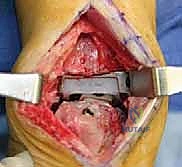

علاج هذه الكسور يتطلب مهارة فائقة من الدكتور محمد هطيف، حيث يتم استخدام تقنيات الجراحة الميكروسكوبية وتثبيت الكسور باستخدام صفائح معدنية دقيقة ومسامير (Locking Plates) دون المساس بثبات المفصل الصناعي، أو يتم دمج علاج الكسر ضمن عملية مراجعة المفصل الكلية إذا كان المفصل نفسه تالفاً.

الخطوة الثانية: النهج الجراحي (Surgical Approach)

يتم فتح الشق الجراحي الأمامي القديم بحذر شديد لتجنب إتلاف الأوعية الدموية والأعصاب، وهنا تبرز أهمية تقنيات الجراحة الميكروسكوبية التي يتقنها الدكتور هطيف.

الخطوة الثالثة: إزالة المفصل القديم (Explant Removal)

يتم استخراج المكونات المعدنية والبلاستيكية لمفصل (Agility) القديم بحرص بالغ للحفاظ على ما تبقى من العظم السليم.

الخطوة الرابعة: تنظيف العظم والترقيع (Debridement and Bone Grafting)

يتم تنظيف الأنسجة الملتهبة والأكياس العظمية. ونظراً لأن مفصل (Agility) يترك فراغاً كبيراً بعد إزالته، يتم استخدام طعوم عظمية (Autograft من حوض المريض أو Allograft من بنك العظام) لملء الفراغات وبناء أساس قوي.

الخطوة الخامسة: تركيب المفصل الجديد أو الدمج

يتم إدخال المفصل الجديد المخصص للمراجعة، والذي يحتوي غالباً على سيقان (Stems) تدخل عميقاً في عظمة الساق وعظمة الكاحل لضمان الثبات الميكانيكي. في حال وجود كسور في الكعب، يتم تثبيتها في هذه المرحلة.

الخطوة السادسة: الإغلاق التجميلي

يتم خياطة الأربطة والأنسجة الرخوة والجلد بطرق تجميلية دقيقة لتقليل الندبات وسرعة الالتئام، ثم توضع القدم في جبيرة خلفية واقية.